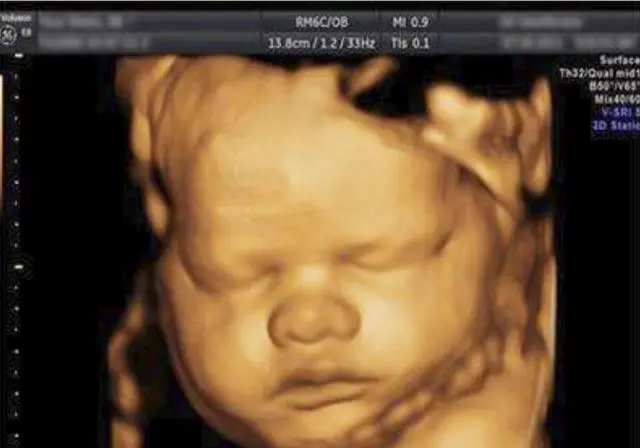

首先,四维彩超可以更加清晰地观察胎儿的发育情况,及时发现一些异常情况。通过四维彩超可以看到胎儿的面部特征、四肢动作等,有助于医生判断胎儿是否有先天性畸形。这对于早期发现并治疗胎儿异常是非常有帮助的。

其次,四维彩超可以帮助医生检查胎儿的器官是否正常发育。通过四维彩超可以看到胎儿心脏、脑部、肾脏等器官的情况,及时发现问题并采取相应措施。这对于预防和治疗胎儿畸形起到了积极的作用。